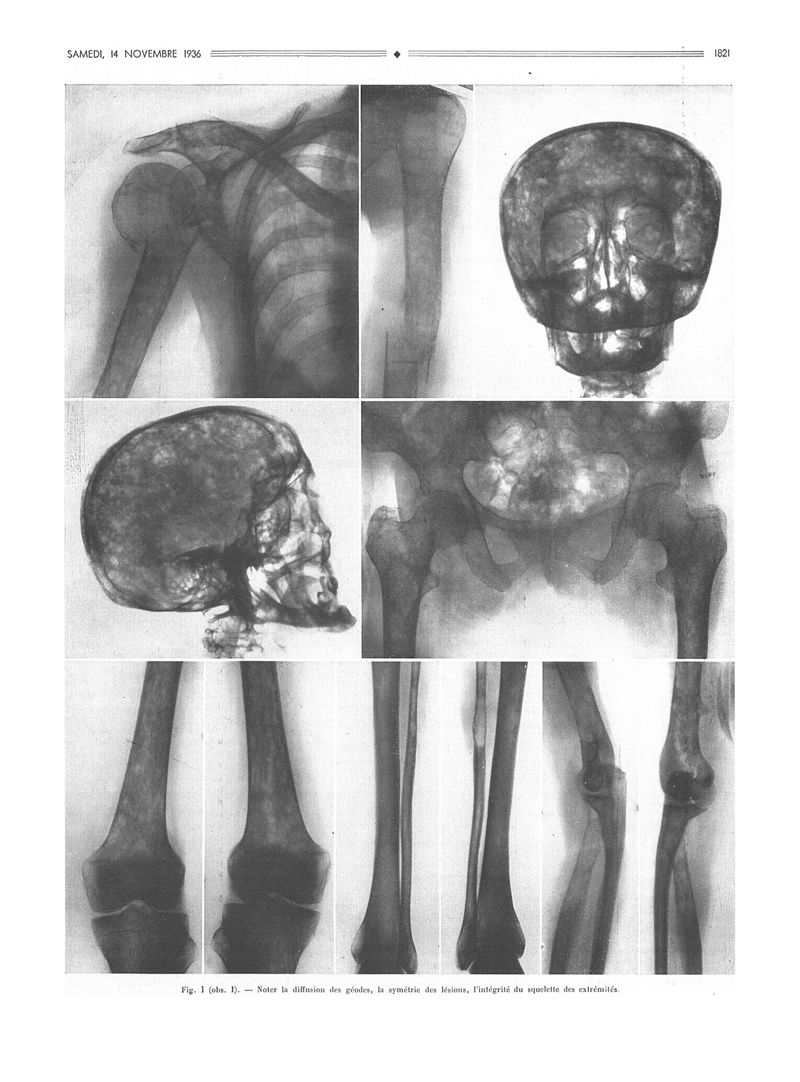

La Presse médicale - [Articles originaux]

1936, Articles originaux. - Masson et Cie, 1936.